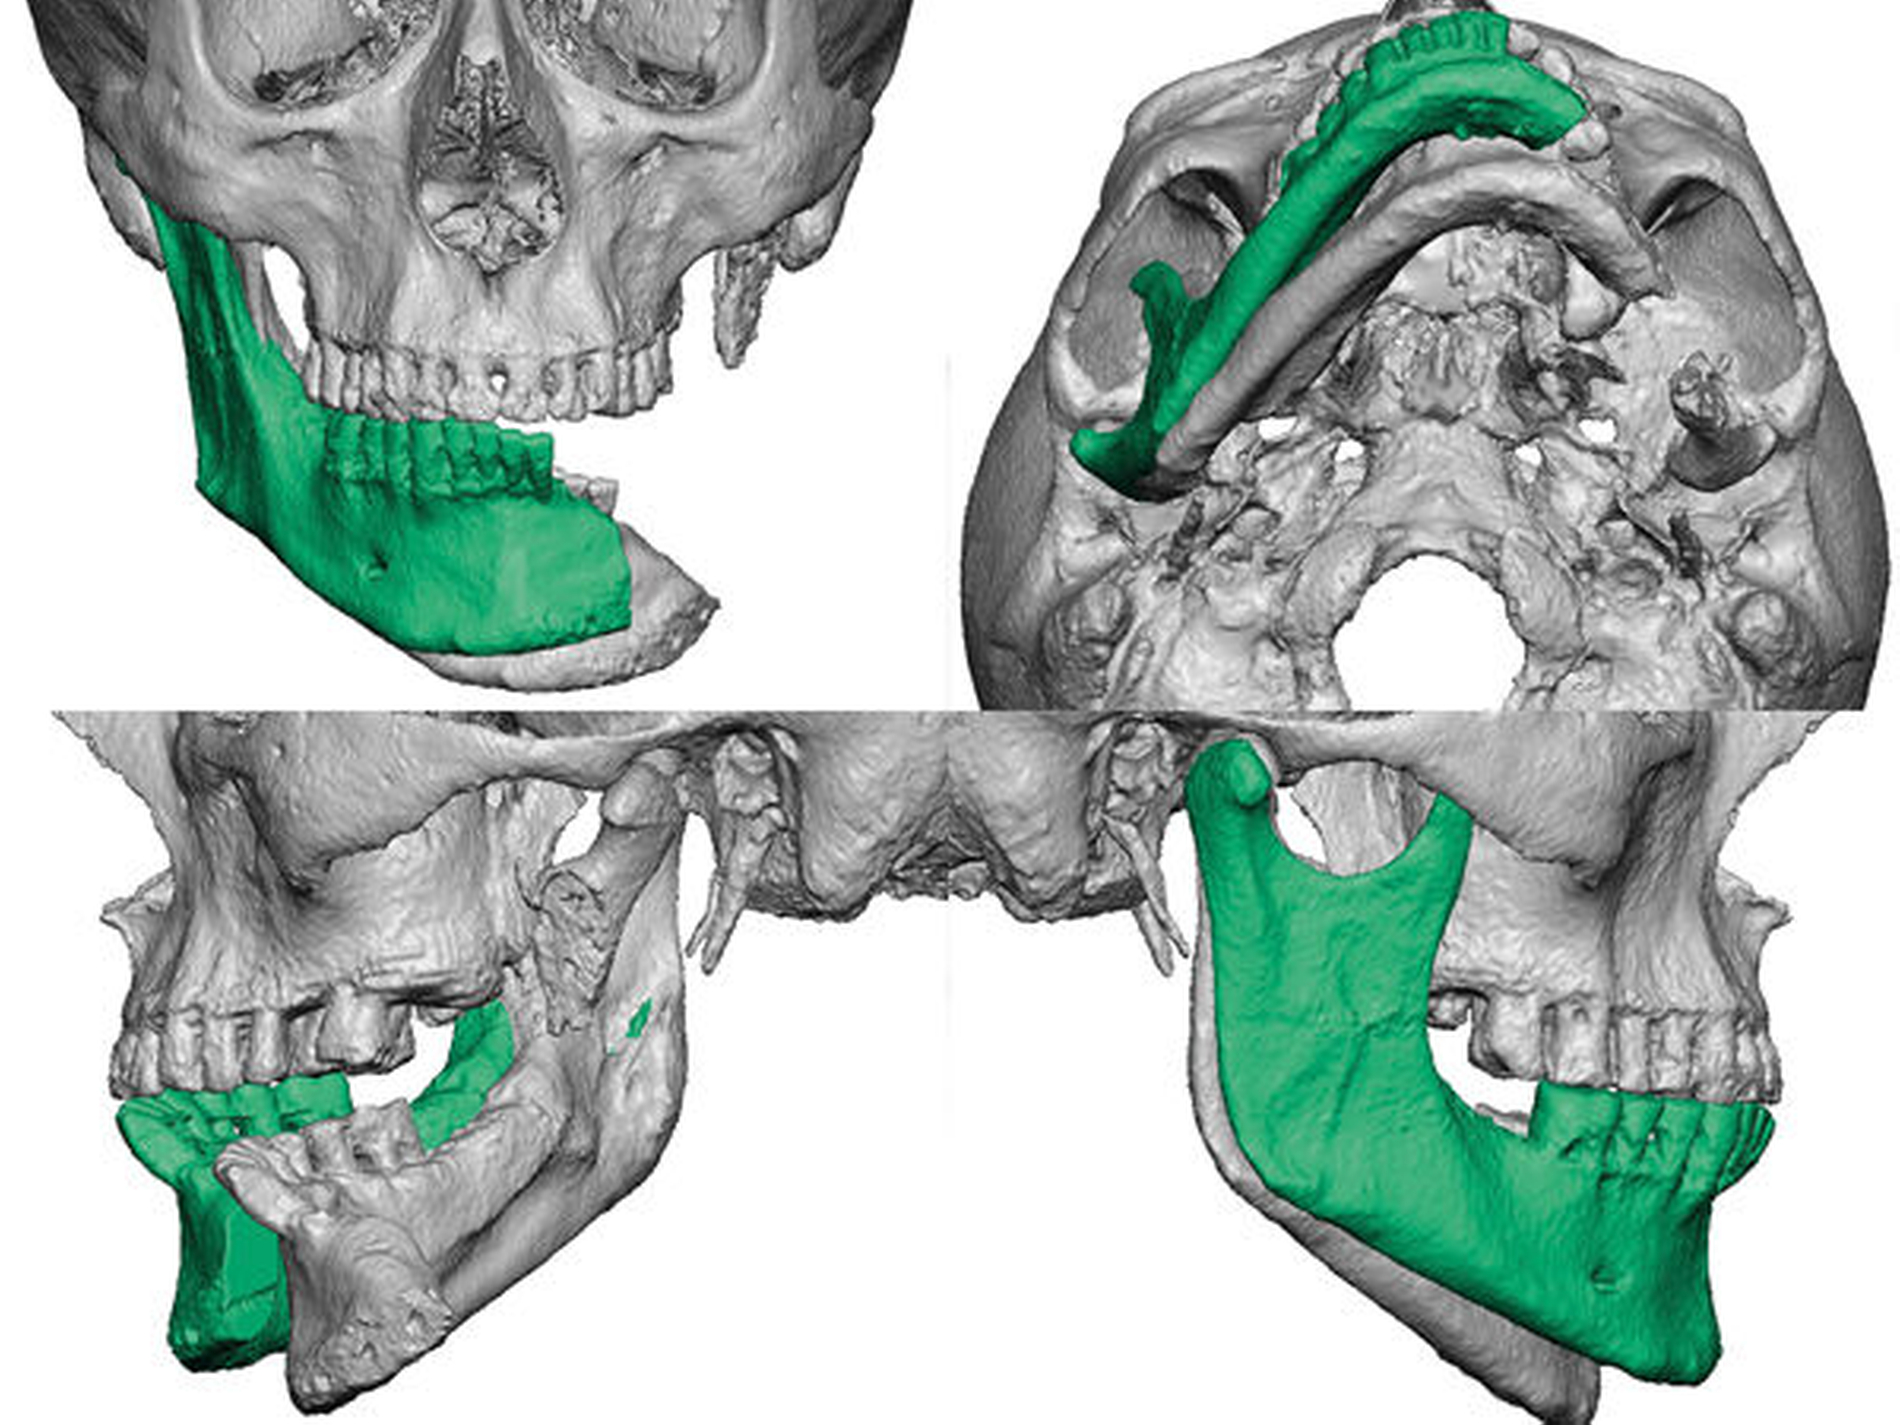

Im Zuge der Forschung und Entwicklung wurde es möglich, auch große Knochentransplantate virtuell präoperativ zu planen, wobei einer der anspruchsvollsten chirurgischen Eingriffe die langstreckige Rekonstruktion der Mandibula ist.

Hier findet weltweit am häufigsten das mikrochirurgisch reanastomisierte Fibulatransplantat für die Rekonstruktion Anwendung [Peled et al., 2005]. Durch die virtuelle präoperative Planung, Schneideschablonen - sogenannte cutting guides - und einem Patient Specific Implant (PSI) kann bei strikter Einhaltung der Protokolle ein exakteres Operationsergebnis erzielt werden [Hanken et al., 2015; Wilde et al., 2015].

Im hier dargestellten Fall werden die Möglichkeiten der virtuellen Operationsplanung von einem mikrochirurgisch reanastomisierten Knochentransplantat in Kombination mit einer individuellen alloplastischen Kiefergelenktotalendoprothese (TEP) und der nachfolgenden guided-surgery-Implantation zur Vorbereitung eines implantatgetragenen Zahnersatzes gezeigt. Das Langzeitbrückenprovisorium wurde ebenfalls in einer virtuellen Umgebung konstruiert und per CAD/CAM hergestellt.

Die CT-Daten wurde in die Software der Firma 3D Systems (3D Systems, Littleton, USA) eingelesen und aufbereitet. Dadurch ist es möglich, relevante Areale zu segmentieren und bei der Planung virtuell frei zu positionieren. Dies kann in Abbildung 3 gut nachverfolgt werden. Die rotierte Mandibula wurde in ihre ursprüngliche Position und somit die Restbezahnung in Okklusion mit dem Oberkiefer gebracht.

Die neue Okklusion wird postoperativ mittels intermaxillärem Splint gesichert (Abbildung 4). In den Folgeschritten werden die Resektionsgrenzen festgelegt und die notwendigen Fibulasegmente angepasst (Abbildung 5).